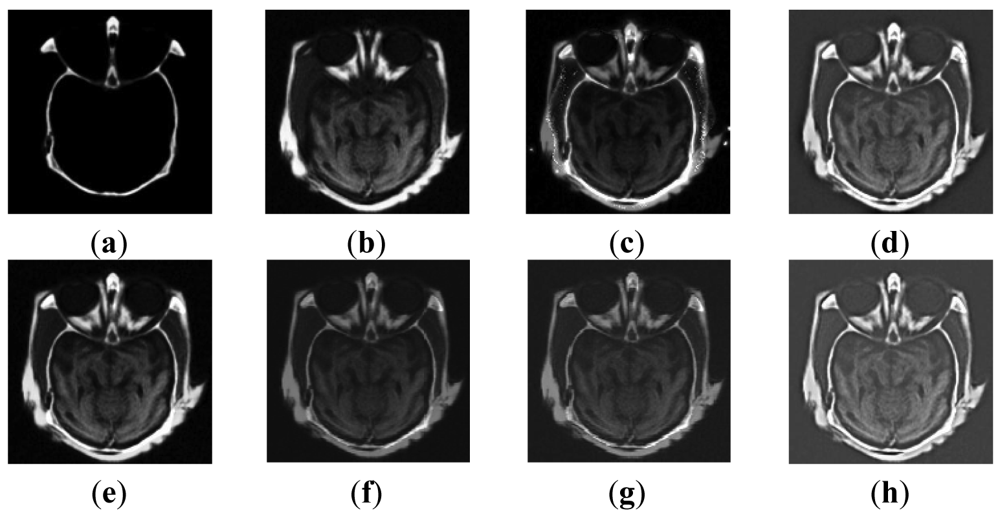

5.3. Medical Image Fusion

Figure 4(a,b) are medical CT and MRI images whose sizes are 256 by 256. Six different methods, including our proposed one, are adopted to evaluate the fusion performance, and the simulated results are shown in Figure 4(c–h).

From Figure 4, images based on methods M2 and M3 are not fused well enough for the information in the MRI source image is not fully described yet. Although the external contour of M1 is clear, the overall effect is poor, which is confirmed by the low brightness of the image and the appearance of some undesirable artifacts observed on both sides of the cheek. Oppositely, PCA, wavelet and our methods not only produce distinct outlines and rationally control the brightness level, but also preserve and enhance image detailed information well. Related evaluations are recorded in Tables 4 and 5.

As revealed in Table 4, the proposed method is nearly the best based on the fact that the metrics of IE, SD, AG, PSNR of Figure 4(h) are all greater than that of the former four algorithms (percentages are not listed). The IE value of M1 is the lowest, which is precisely in accord with the image. Our method possesses an AG index of 29.209 which implies the image is clearer than images based on other approaches. In PSNR and SD, our method performs well, being second only to the wavelet approach, and the SD of M1 beats that of M2 and M3. As to Q index and MI, our method takes the second place in MI and the first place in Q, which indicates that the details and edges from source images are well inherited. These details and edges are extremely important for medical diagnosis. Like in experiment 1, our method achieves the lowest values both in AEaF and AEbF, and that of wavelet, M3, PCA, M2 and M1 arrange in ascending order.